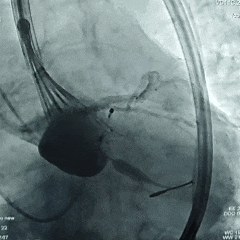

20mm球囊后扩张

瓣膜后扩后造影测压,无压差